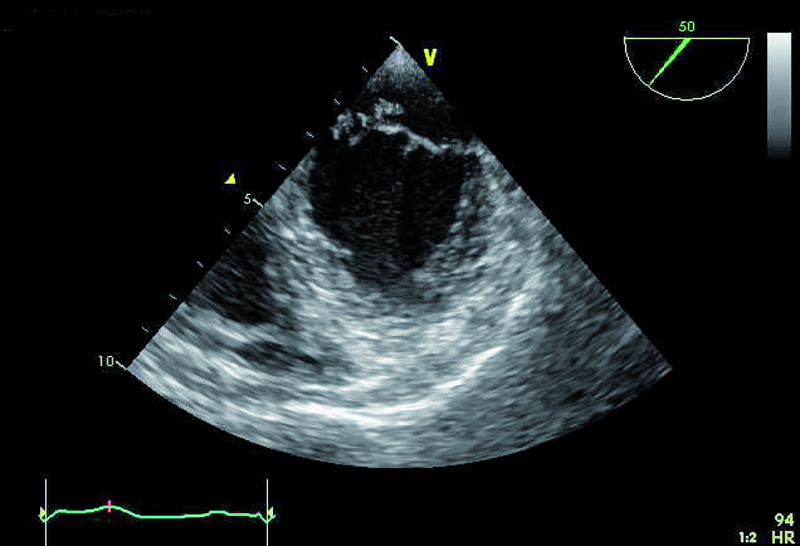

Badanie przezklatkowe, które jest badaniem pierwszego wyboru w przypadku podejrzenia zapalenia wsierdzia, potwierdza obecność dodatkowego echa na strukturach zastawki mitralnej (ryc. 1, 2). Wskazanie konkretnego elementu zastawki, stanowiącego podstawę dla rozwijającej się wegetacji, jest jednak trudne. Badanie przezprzełykowe pozwala lepiej zobrazować punkt wyjścia wegetacji, stopień destrukcji płatka i istotność fali zwrotnej. Szczegółowa ocena zastawki wymaga zastosowania wielu projekcji i płaszczyzn obrazowania, a także znajomości anatomii i relacji przestrzennych poszczególnych struktur. Kryterium orientacyjnym w ocenie jest to, że płatek przedni zastawki mitralnej leży zawsze blisko aorty. Jeśli aorta jest widoczna, zazwyczaj sąsiadują z nią segmenty A1 i A2. Blisko uszka lewego przedsionka leżą natomiast segmenty płatka przedniego i tylnego: A1 i P1. Zawsze warto uwzględnić projekcję i płaszczyznę, w jakich zastawka jest oceniana. Jeśli jest to projekcja dwujamowa z widocznym uszkiem lub jego częścią, to układ segmentów, rozpoczynając od uszka, jest następujący: P1, A2 i P3. Dodatkowe echo zatem widoczne przy spoidle tylno-przyśrodkowym w obrazowaniu przezprzełykowym (ryc. 3, 4) związane jest z segmentem najbardziej dystalnym w stosunku do uszka, a więc z segmentem P3.